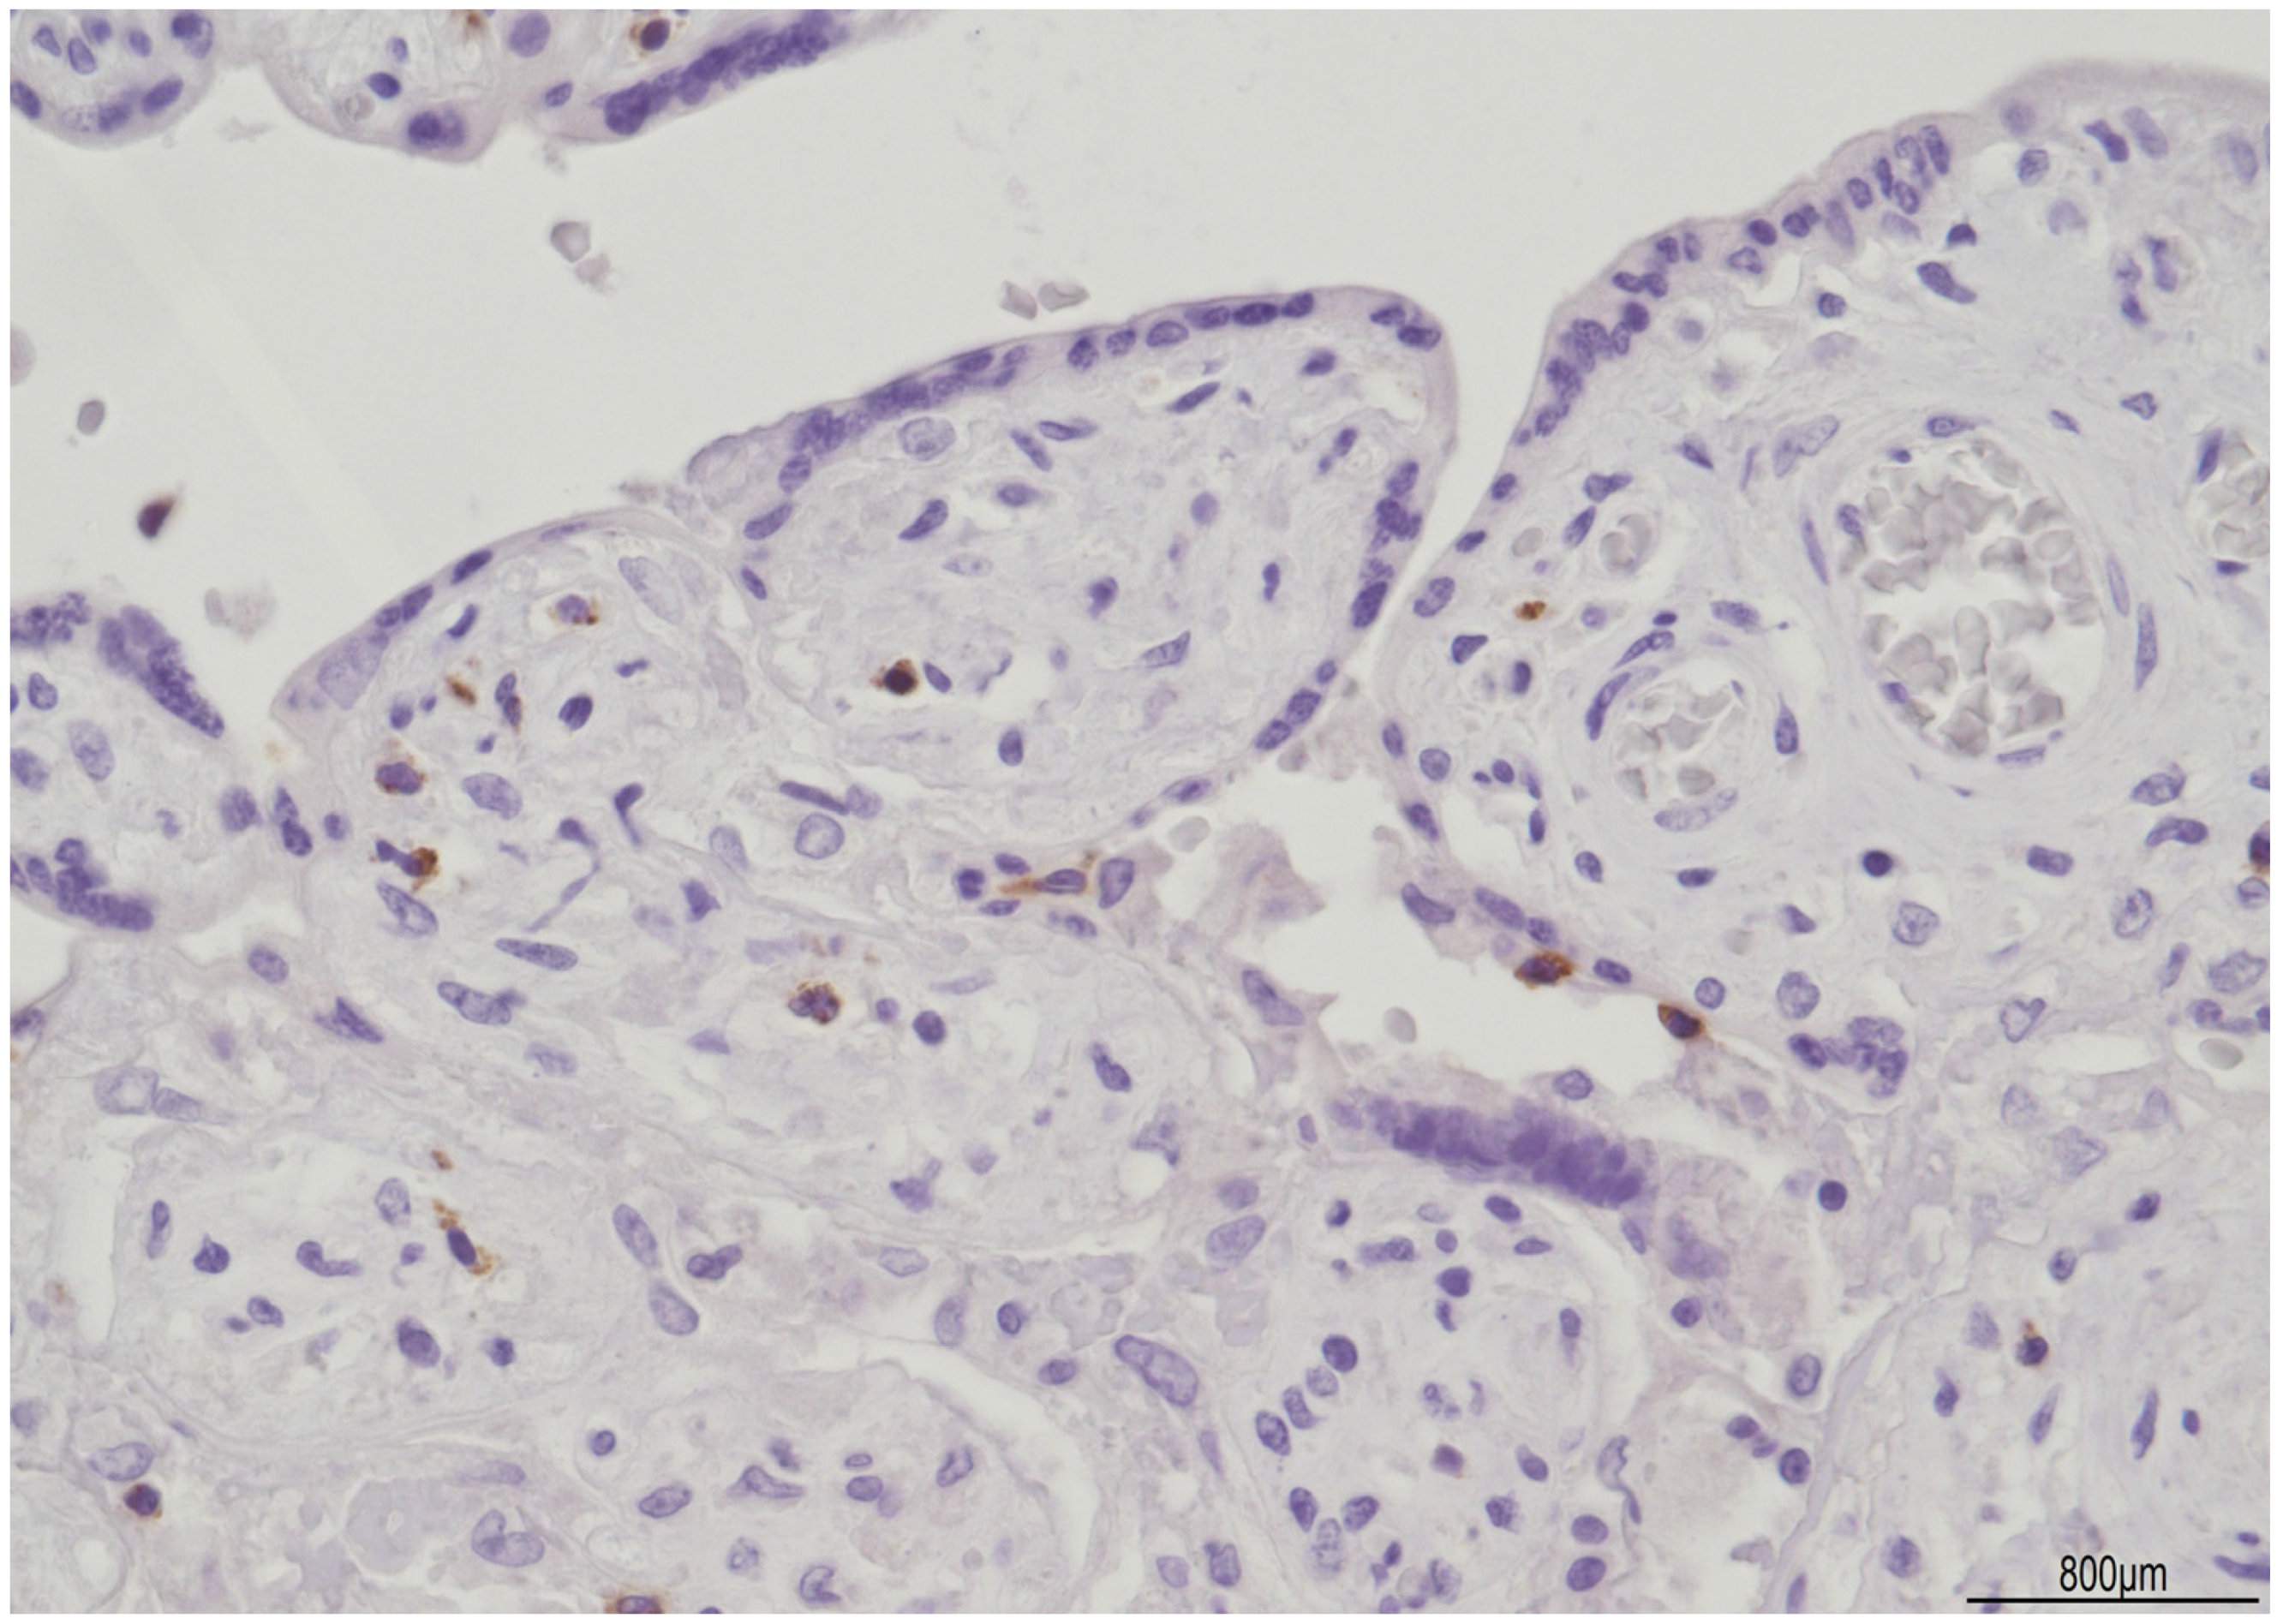

Discordant Eosinophilic/T-Cell Chorionic Vasculitis in a Dichorionic Diamniotic Placenta

Silvestri, E.; Servadei, F.; Tamagnini, I.; Moretti, L.; Bonasoni, M.P. Discordant Eosinophilic/T-Cell Chorionic Vasculitis in a Dichorionic Diamniotic Placenta. Int. J. Mol. Sci. 2023, 24, 9207. https://doi.org/10.3390/ijms24119207